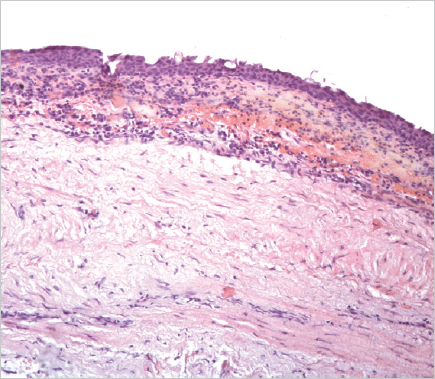

Histological examination of the removed paraurethral cyst was performed (Fig. 6–8).

Fig. 7.The wall of the paraurethral cyst, surgical material. Hematoxylin-eosin staining, ×100. Epithelium with signs of dystrophia and minimal desquamation are represented

Рис. 7.Стенка парауретральной кисты, операционный материал. Окраска гематоксилином и эозином, ×100. Эпителий с признаками дистрофии и минимальной десквамации